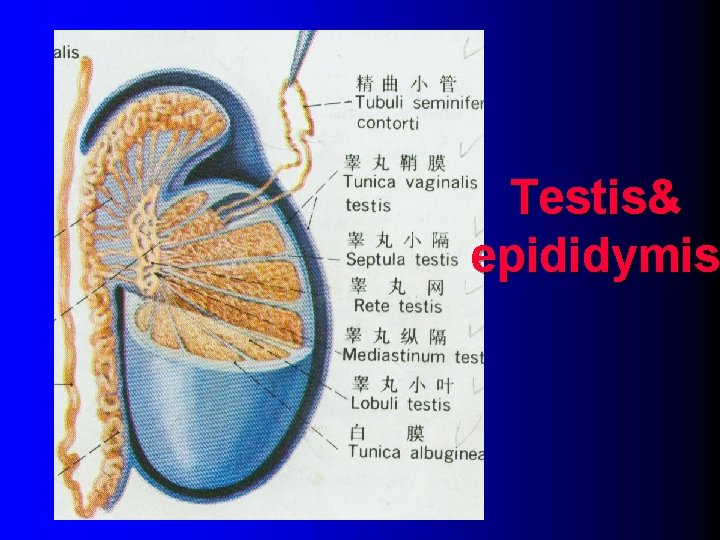

bladder Seminal vesicle prostate Bulbourethral gland Corpus cavernosum Ductus deferens Corpus spongiosum Ductus epididymis Efferent ductule Rete testis Straight tubule Seminiferous tubule epididymis testis Tunica vaginalis

Testis& epididymis

(三)straight tubule & rete testis l Straight tubule: near the mediastinum of the testis , where seminiferous tubule assume a short straight course. l Rete testis: the straight tubule empty into the rete testis, an anastomosing channel system within the mediastinum. l Sperm produced in seminiferous tubule pass by straight tubule & rete testis , leaving testis and arriving in epididymis.